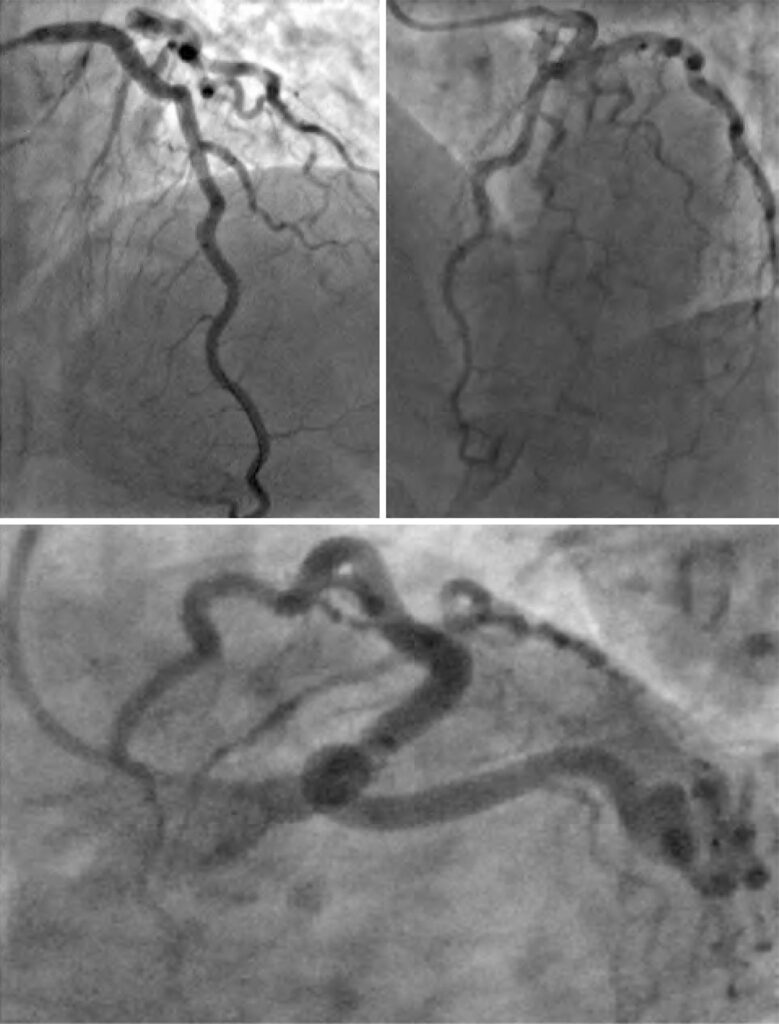

Spontaneous coronary artery dissection is defined as non-iatrogenic epicardial coronary dissection, not associated with atherosclerosis or trauma. Myocardial injury occurs due to coronary artery obstruction caused by intramural hematoma or intimal disruption, rather than atherosclerotic plaque rupture or intraluminal thrombus. We report a case of type 2 variant A spontaneous coronary artery dissection in the mid left anterior descending artery, presenting with type A Wellens’ syndrome, which required percutaneous coronary intervention for relief of refractory angina and pulmonary congestion.